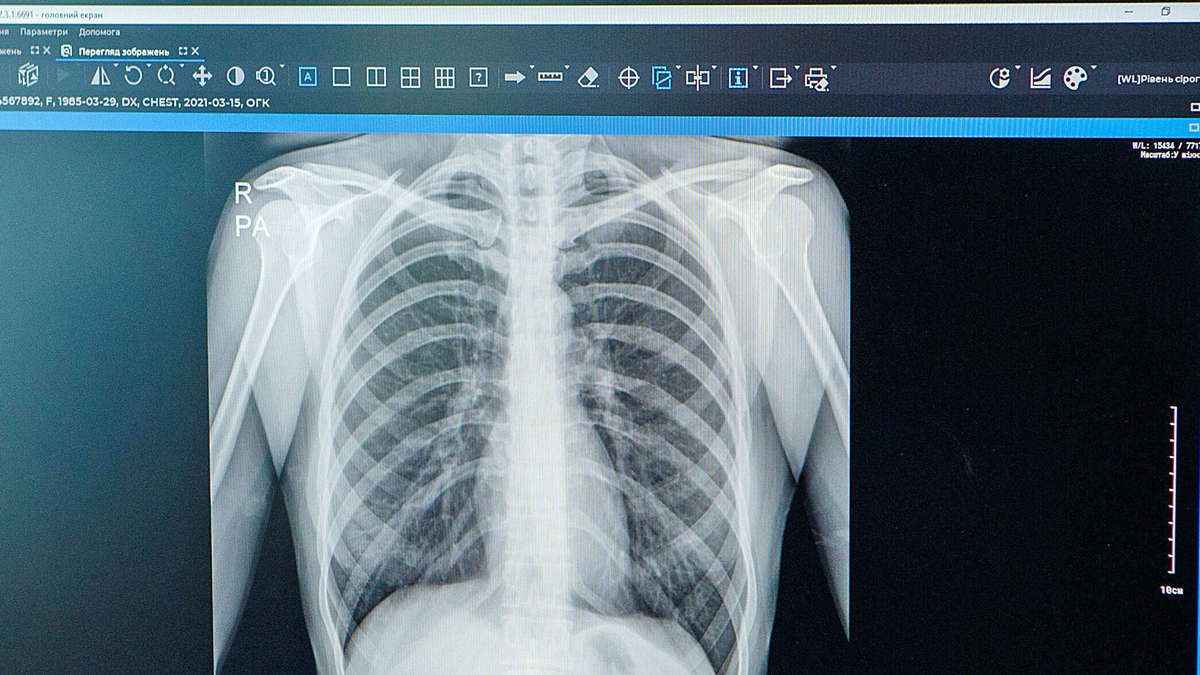

Adamın midesinin röntgeni çekildiğinde şoke edici gözüntü gözler önüne serildi. Adamın midesi, bazıları 10 santimetreye kadar ulaşan büyüklükteki çivi ve vidalarla doluydu.